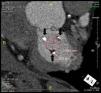

Based on our experience with three cases of transcatheter double valve (aortic and mitral) implantation by a transapical approach, we describe the essential steps in preprocedural planning using multidetector computed tomography (MDCT). The first step is to identify the brand and size of the previously implanted bioprosthesis. The true internal diameter of this valve is then determined by MDCT (mean of major and minor axes, Figure 1), which is usually less than the labeled prosthesis size. The true internal diameter should be confirmed by referring to conversion tables or software apps such as ViV® (Valve-In-Valve). The internal diameter between the stent posts of the bioprosthesis is then measured (Figure 2), since if this is less than the true internal diameter due to deformation of the stent posts, it can prevent transcatheter valve-in-valve implantation. This information is then used to select the correct size of the valve to be implanted and the procedure can commence.

MDCT plays an essential role in planning transcatheter mitral valve implantation, to determine the true internal diameter of the dysfunctional bioprosthesis, select the correct size of the replacement valve and prevent periprocedural complications such as the valve becoming wedged against the stent posts, paravalvular leak or valve migration.